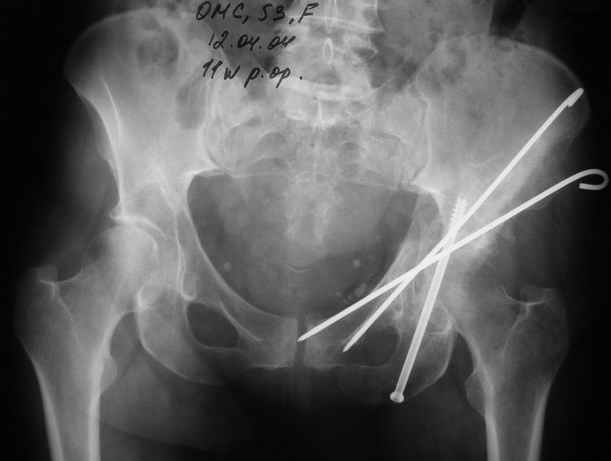

К сожалению, набора для ретроградного или антеградного реконструктивного штифтования в операционной нет, поэтому доставка заняла н-ное время. Вопрос, который возник у меня- по поводу оптимальной тактики хирургии: вся фиксация в один этап из расширенного доступа или последовательно сначала бедро и позже реконструкция впадины, комбинированный доступ к впадине отдельно к передней и задней колоннам или из расширенного илеофеморального одного доступа. Все-таки решил остановиться на одноэтапном подходе и спустя 5 дней (как раз и наборы привезли) из расширенного илеофеморального доступа сначала фиксировал реконструктивным штифтом Smith&Nephews бедро и

шейку (благо перелом шейки 2 типа -относительно стабильный) затем фрагмент крыла подвздошной кости Lag screw, далее пластина на заднюю колонну и винты в переднюю колонну.(с размерами и направлением винтов ошибка вышла:-((, но интраоперационно у меня была полная уверенность , что винты *ушли* в лонную кость).

Еще раз спасибо за комментарии и готовность помочь с имплантами. Постоп картинки в приложении,

12.04.04